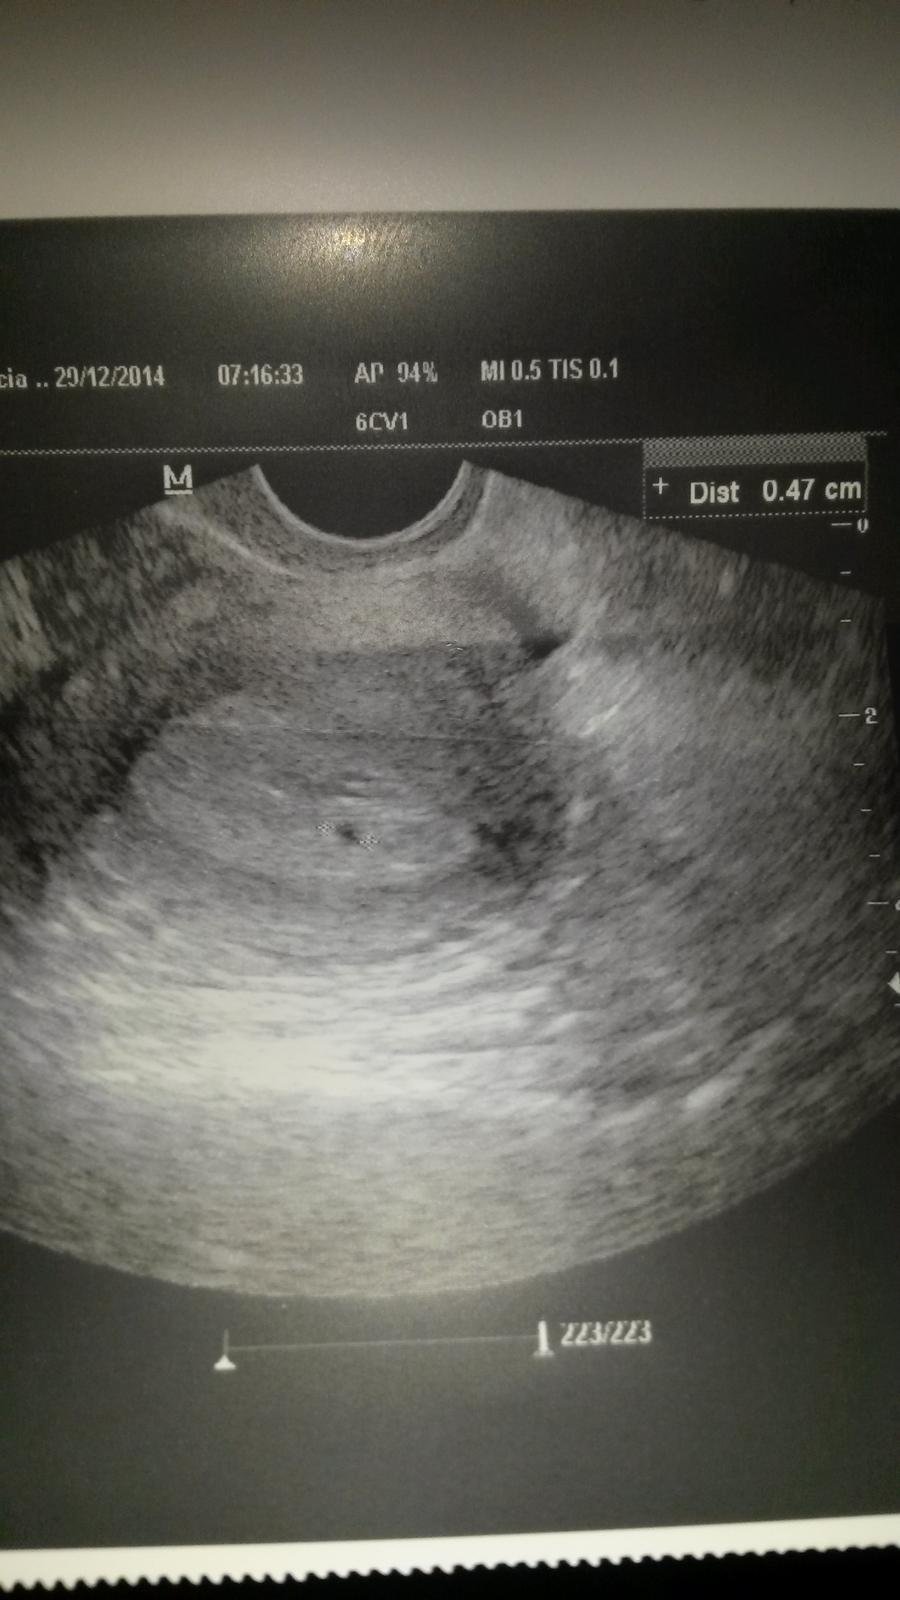

Ahojte kocky. Tak to vyzera ze asi budem k vam patrit. Podla mrsky mi vychadza termin na 2.9 2015 ci to tak bude uvidime. Ja som po KET zatial to vyzera slubne i ked nam troska pomalsie stupa hcg. Bola som v pondelok u dr koli 5 dnovemu spineniu a robila aj sono. Videli sme malinku dutinku. Dufam ze je vsetko ok a nemala byt uz vacsia.uz mam 2 potraty za sebou tak dufam ze toto dotiahneme do stastneho konca.na sone som bola 4+5 tt podla mrchy.